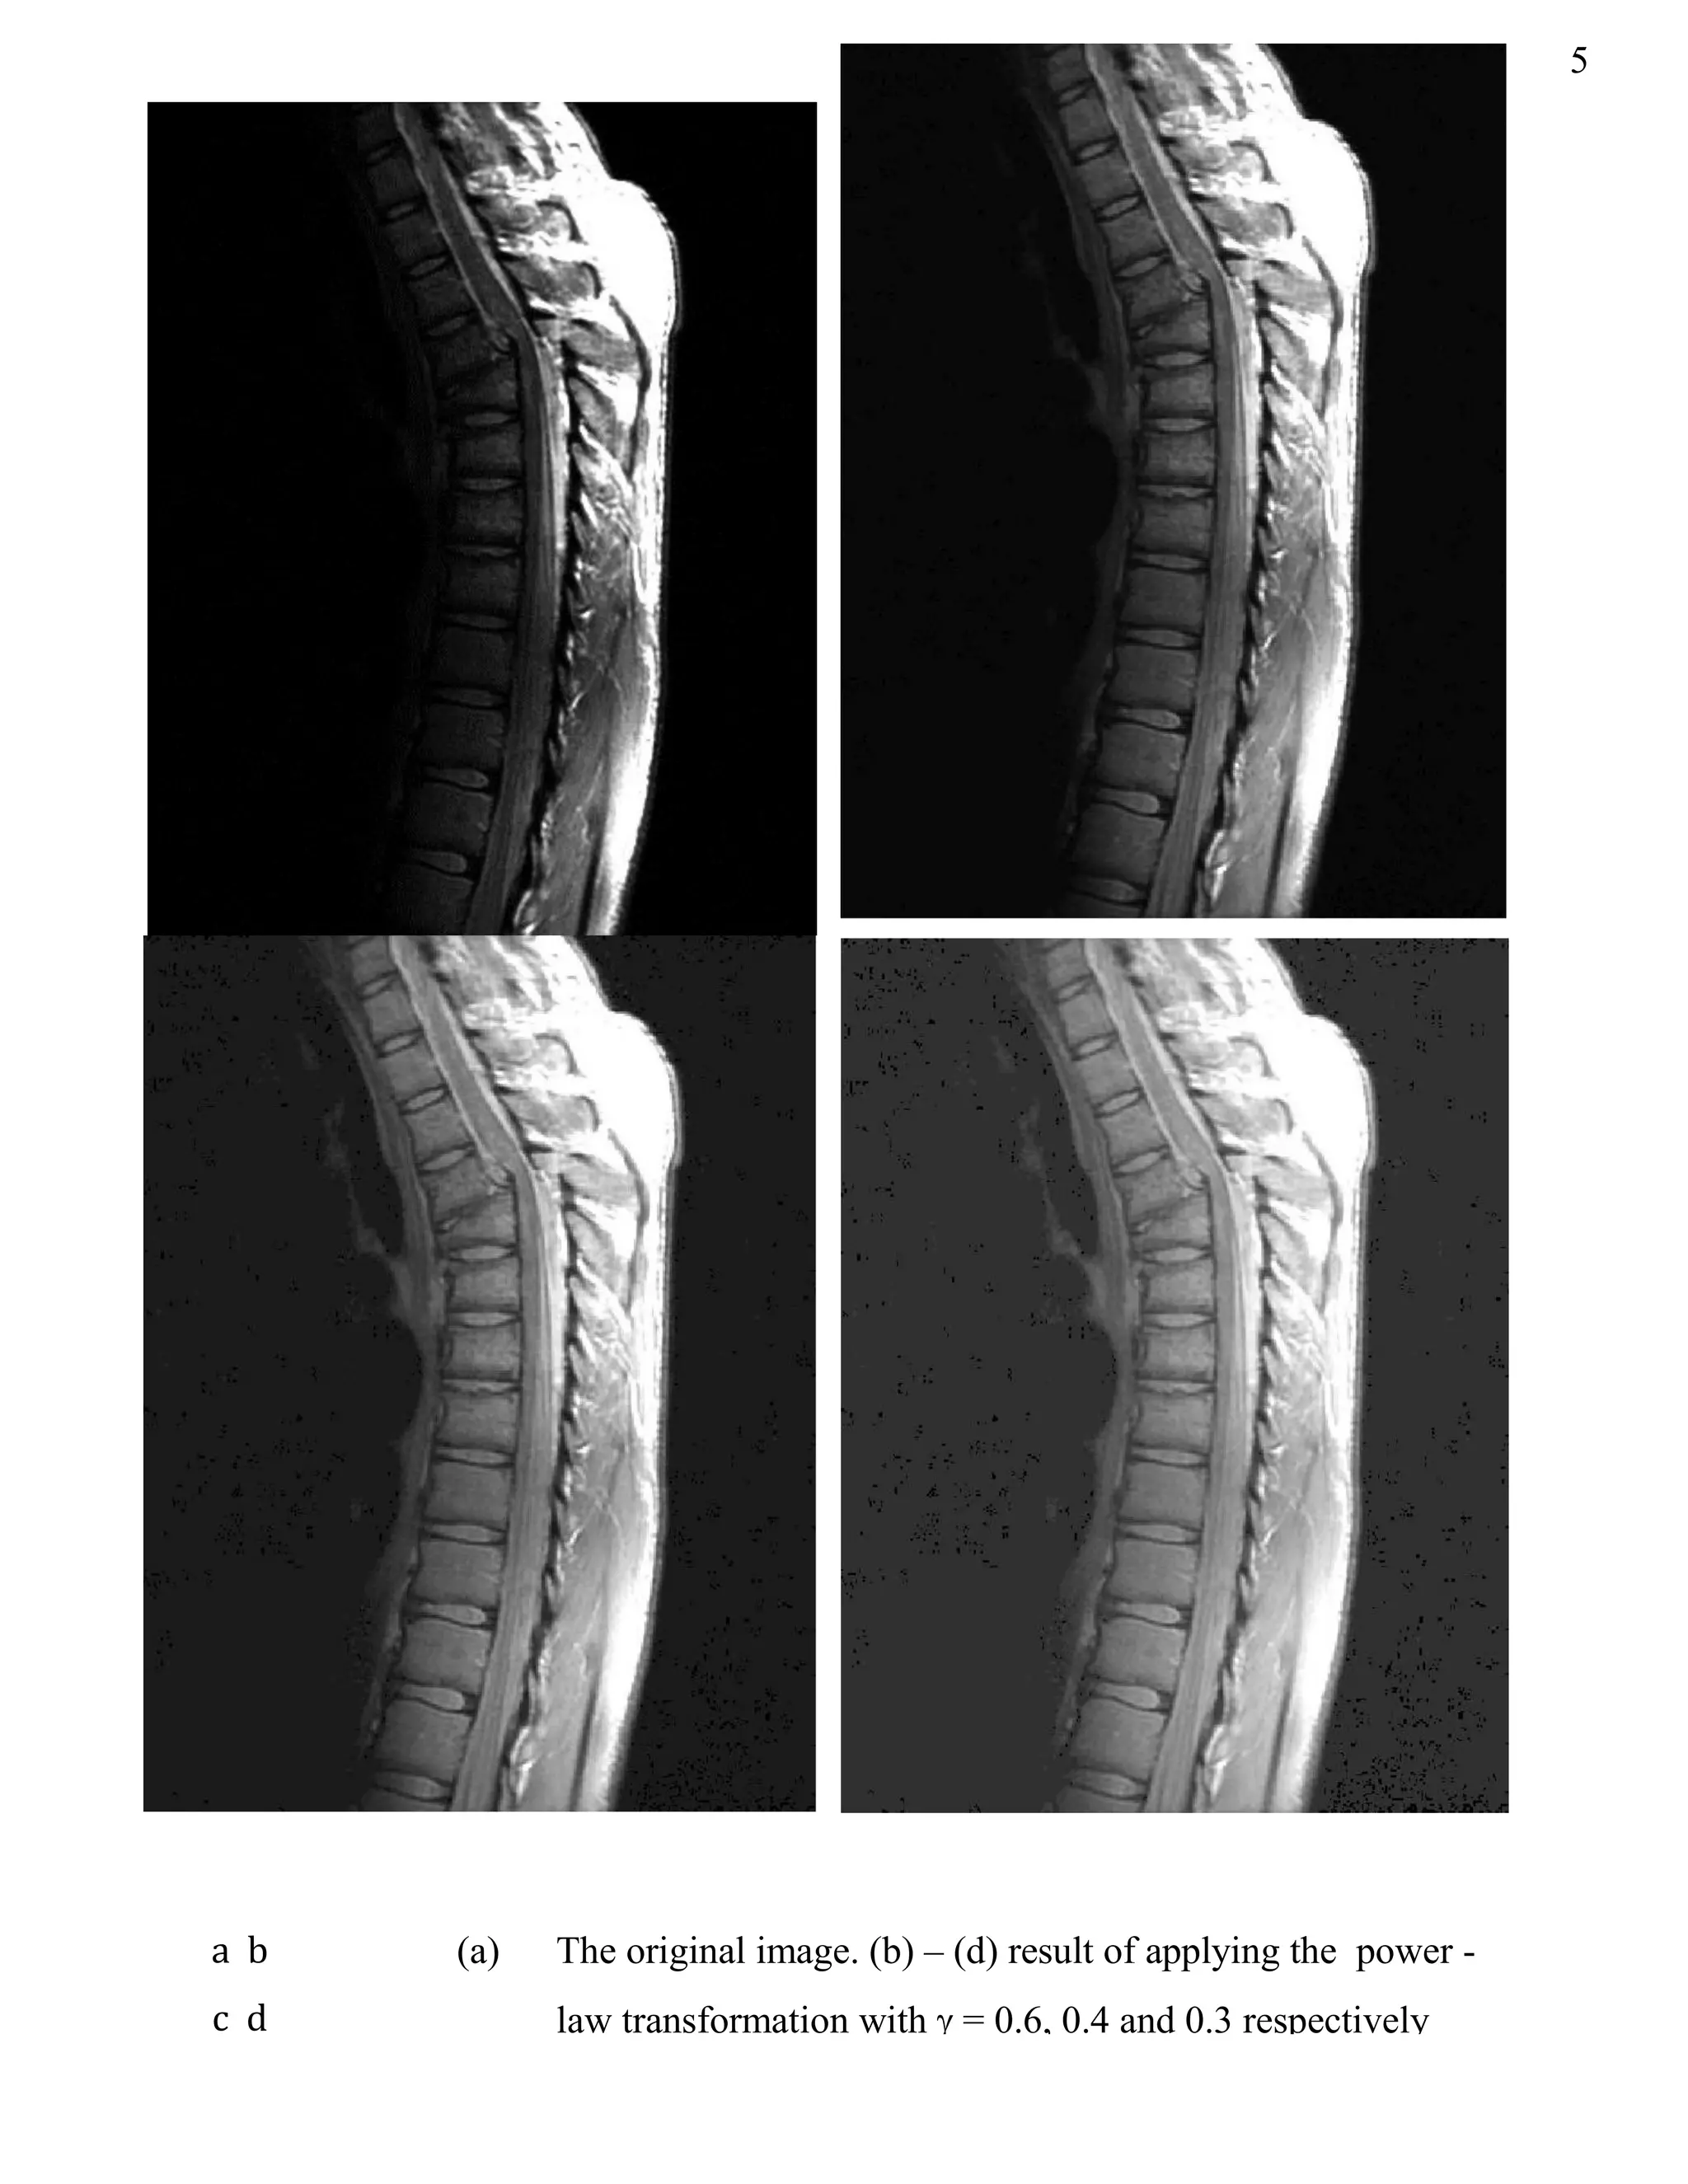

With  = 0.6, 0.4 and 0.3 respectively, we can get three images respectively, as shown in the

following figure,

a b

c d

(a) The original image. (b) – (d) result of applying the power -

law transformation with  = 0.6, 0.4 and 0.3 respectively